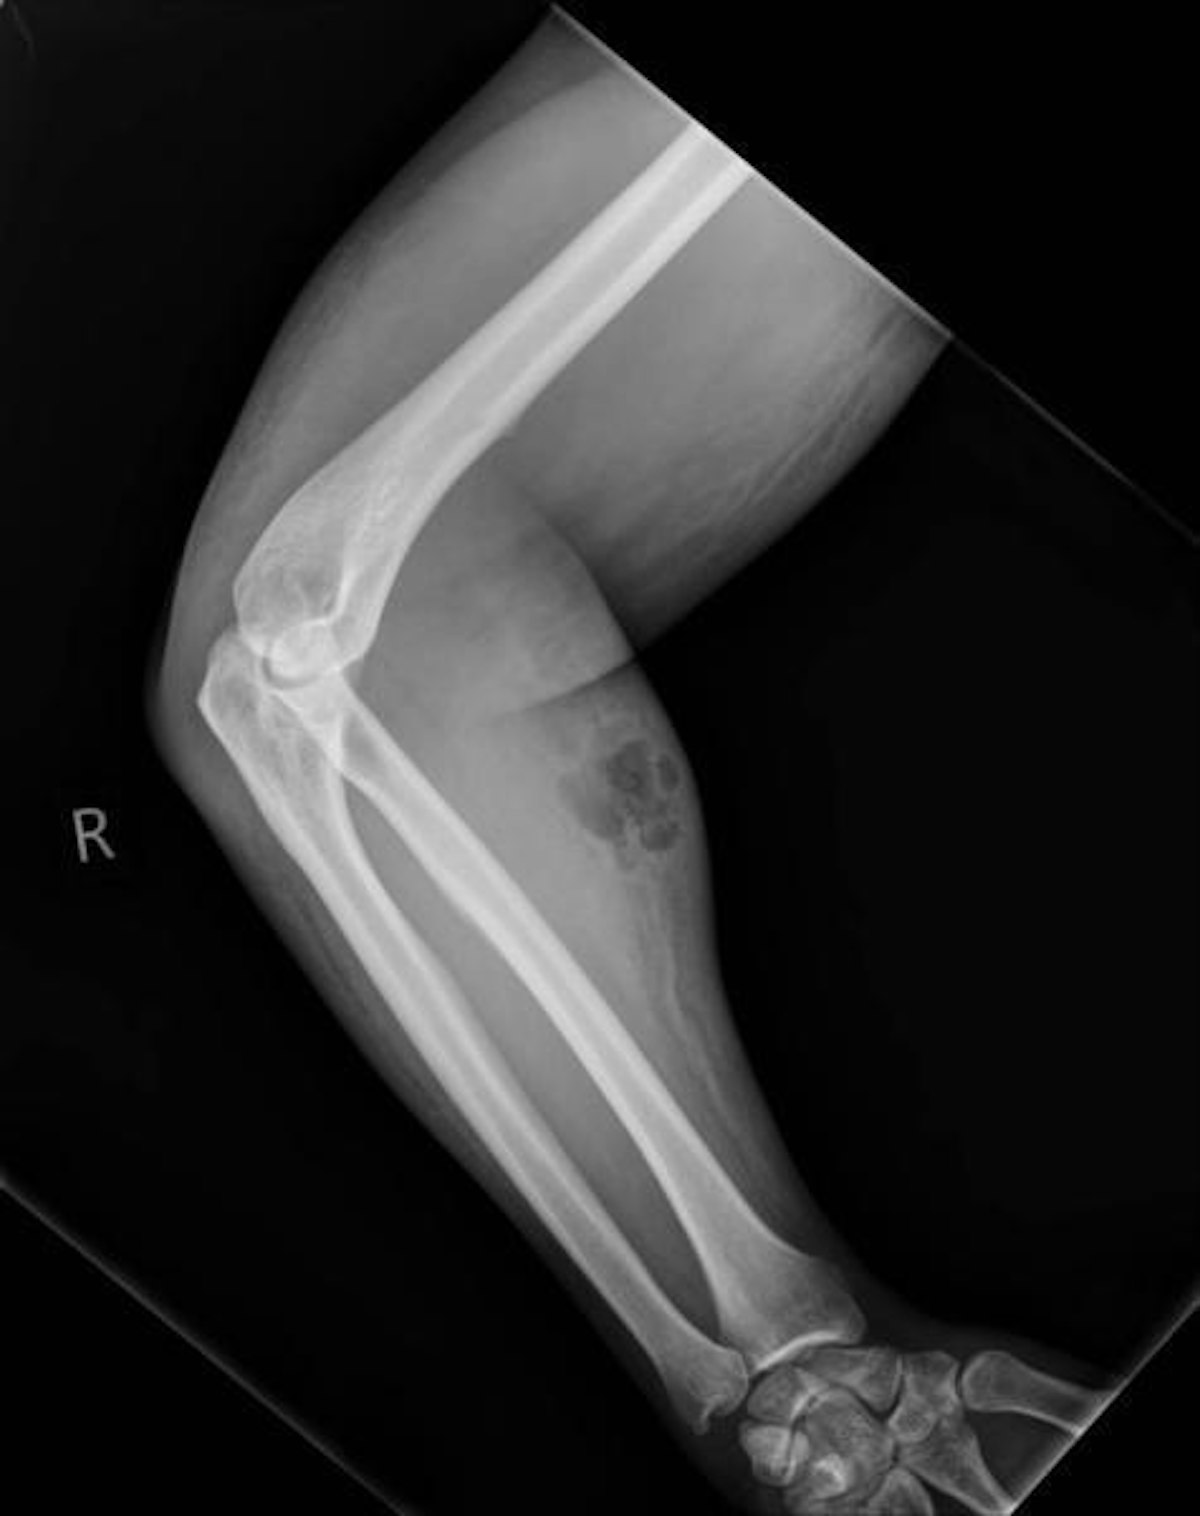

• 2 /4 Röntgenbilder brachten Licht ins Dunkel: Unter der Haut des Mannes hatte sich ein großer Abszess gebildet. Wie es dazu gekommen war, offenbarte der 33-Jährige erst nach und nach. Am Ende stellte sich heraus, dass er versucht hatte, seine Rückenschmerzen mithilfe einer "alternativen Heilmethode" zu kurieren.

(Bild: IMJ/L.Dunne et al.)

• 3 /4 Während rund 18 Monaten hatte sich der Ire immer wieder sein eigenes Sperma injiziert. Zuletzt hatte er die Dosis deutlich hochgeschraubt und sich diese sowohl intravenös als auch intramuskulär verabreicht. Offensichtlich keine gute Idee.